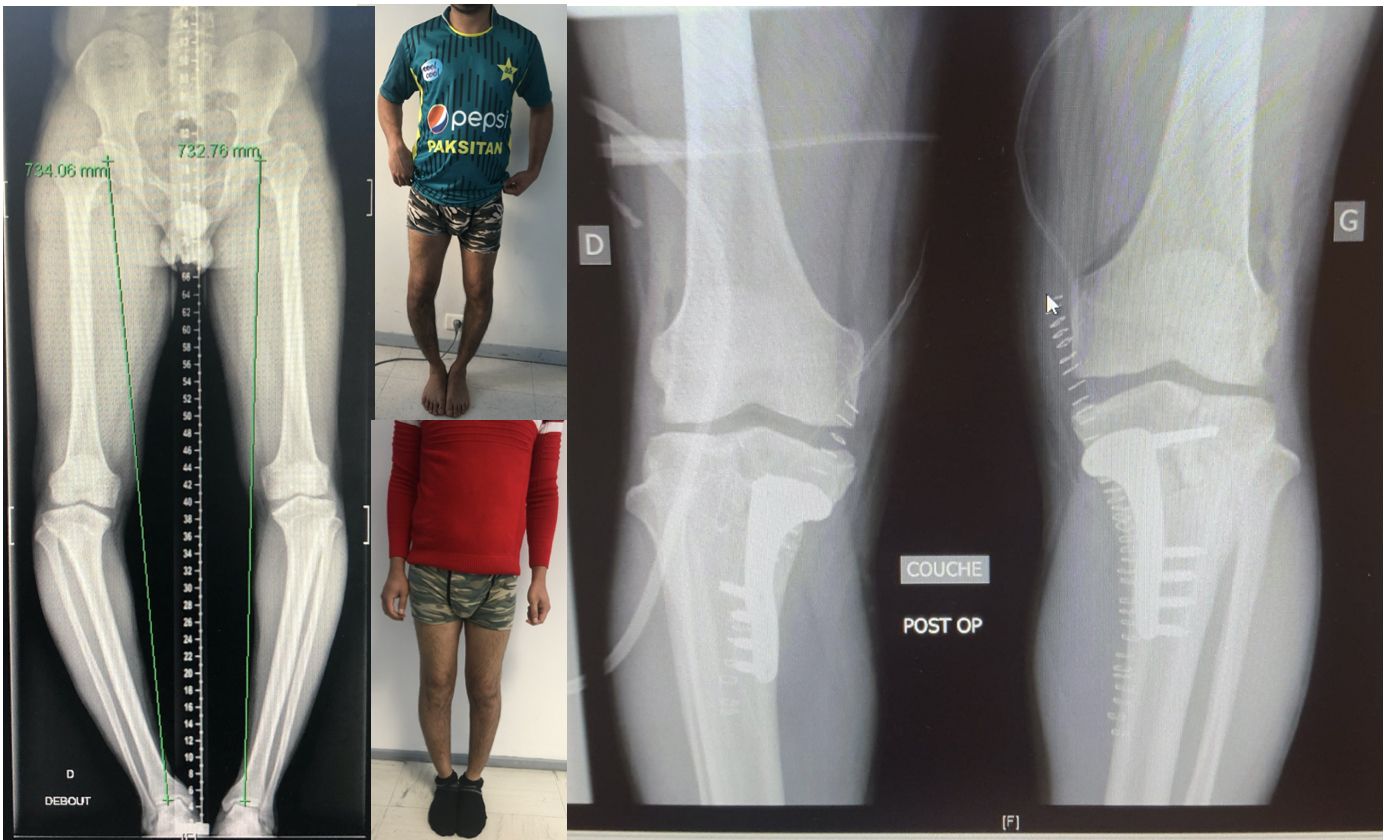

In the vast majority of cases knee osteotomy aims to correct an extra-articular deformity by shifting the mechanical axis from the overloaded femoro-tibial compartment to the contralateral side to unload cartilage and subchondral bone [12]. By correcting a pre-existing tibial or femoral metaphyseal abnormality the natural evolution of knee arthritis might be slowed down. The Hip-Knee-Ankle (HKA) angle is usually used to estimate the overall alignment of the lower limb. This angle represents the result of three components: the bony alignment of the femur and tibia as well as the intra-articular deformity resulting from articular surface wear at the concave and soft-tissue laxity on the convex side of the deformity. To allow proper planning of the bony correction the deformity analysis, introduced by D. Paley long time ago, is mandatory[13]. This includes the Lateral Distal Femoral Angle (LDFA), the Medial Proximal Tibia Angle (MPTA) as well as the Joint Line Convergence Angle (JLCA). The LDFA is defined by the angle between the femoral mechanical axis and the articular surface of the distal femur. The MPTA is defined by the angle between the tibial mechanical axis and the articular surface of the proximal tibia. The JLCA best reflects cartilage wear, meniscus loss and soft-tissue laxity of the contralateral side. (Figure 1 A-B-C)

Conventional planning

When dealing with a misaligned lower limb, the first step is to analyze if the deformity is located at the Tibia, Femur or both, which will influence where the osteotomy has to be performed. Not all varus knees have the deformity on the tibia only. 10-15% will need a femur or a combined femur and tibia osteotomy for correction, otherwise the jointline will be significantly malorientated. The next step is to decide for the proper postoperative frontal alignment and therefore to plan the desired correction. The planning must be performed on standardized full leg weight bearing X-rays [14]. Traditionally the new weight-bearing line should be within the “Fujisawa” point, which is 62% and 65% of the tibial plateau (with the medial side set at 0% and the outermost lateral aspect at 100%) [15]. Based on this point it is then possible to calculate the amount of correction needed in the frontal plane. One of the most common used technique for this correction angle α calculation is the Miniaci method [16] (Fig 1 D-E). Any existing soft tissue laxity on the concave side of the deformity (JLCA > 2 mm) has to be included in this bony correction angle calculation, otherwise the leg might be overcorrected.

Own preliminary results

We performed more than 300 PSCG osteotomy cases in the last 5 years, and we already published the accuracy of the correction obtained in both specimens [9], ten first [7] and hundred first HTO and DFO patients [10,21] as well as the learning curve of the system [11]. We also Investigated on several improvement such as the hinge protective K-wire [18,19] or the influence of saw-blade geometry [22]. Overall, the precision of the system in both coronal and sagittal plane was 1+/- 1° and after 10 cases the mean operative time dropped below 30 minutes with 6 intraoperative fluoroscopic images taken only [10,11]. The clinical results of our patients involved in impact sports showed better results compared with patients undergoing unicompartmental knee arthroplasty [23].